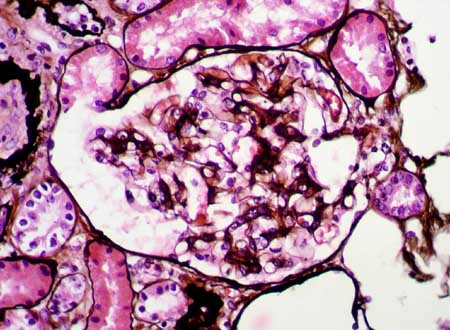

Figura 3.

En uno de los glomérulos identificamos esta lesión esclerosante

segmentaria. (Trcrómico de Masson, X400)

Figura 4.

La tinción con plata resalta un leve incremento de la matriz mesangial,

sin alteraciones de la pared capilar. (Plata-metenamina, X400)